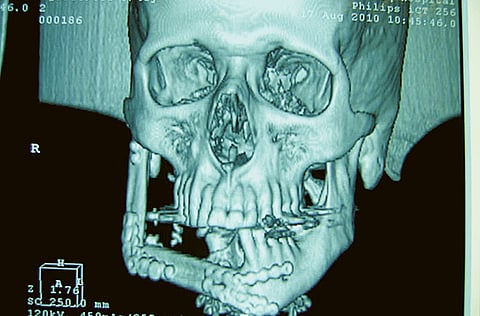

Abu Dhabi: A large, benign tumour that was deforming the face of a 42-year-old man was successfully removed by a team of doctors and surgeons at Mafraq Hospital, which is managed by Bumrungrad International, during a seven hour maxillofacial (head, neck, face and jaw area) procedure on Sunday.

The man suffers from a rare genetic disorder known as Ameloblastoma, which created a curable but potentially recurrent tumour on the right side of his face and neck. Two previous surgeries in other facilities were unsuccessful in treating the growing tumour.

"The tumour was very large, measuring 18cm x 4cm…Surgeries involving the transfer of tissue only have been successfully performed at Mafraq Hospital in the past; however, this procedure involved not just tissue but also bone transfer to reconstruct the patient's jaw… For this case we used the patient's lower leg bone [fibula] in the complicated surgery," Dr A. Nasser Hachem, a cranio-maxillofacial surgery consultant who led the team, explained. During the surgery the man's complete lower jaw (mandible) and floor of his mouth were removed and part of the lymph nodes located on the right side of his neck and 60 per cent of his lower jaw were placed on the right side of the mouth floor to allow surgeons to reconstruct his entire jaw.

Five additional implants, including dental, were also performed to help complete the reconstruction of his lower face.